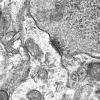

BASIC PROCESSES

Neuroaxonal dystrophy (2)